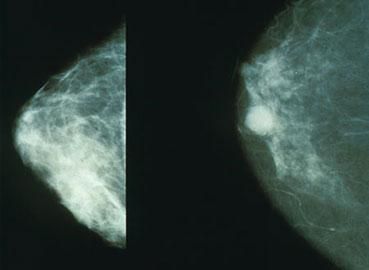

Mammograms like these can pick up breast lumps before they can be felt. The right hand image shows a potentially cancerous lump.

(Photo credit: morning2k, Wikimedia Commons)

Sometimes cancers form lumps that can be detected on the outside of the body, making detection a bit easier. Breast cancer and testicular cancer are both examples of this. Melanoma forms dark moles on the skin surface.